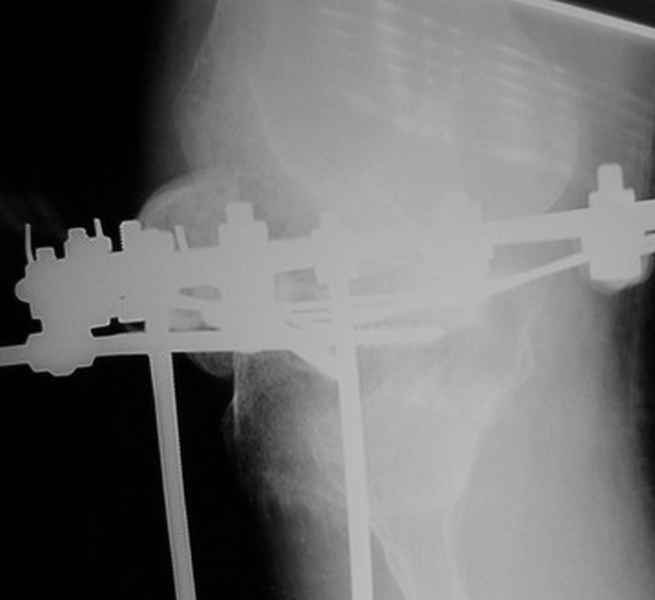

Пациент В. 53 лет, травма в феврале 2009. ДЗ. Открытый оскольчатый перелом нижней трети голени. При боли поступлении выполено ПХО, аппарат Илизарова. В последующем проводили ВХО, резекция костных отломков, укорочение 6 см, рана зажила. Была выполнена остеотомия большеберцовой кости в проксимальном отделе, резекция. Производилось тракция. На последних рентгенограммах выявлено, что одновременно с "выращиванием" регенерата произошло низведение надколенника на длину выращенного регенерата. Клинически: активное разгибание сохранено, объем движений в колене 180-110 градусов. Черными стрелками обозначен верхний край надколенника с одной и с другой стороны. Красная стрелка обозначает пальпируемую связку надколенника. Причина - остеотомия выше места прикрепления связки надколенника. Вопрос: была ли у кого подобная ситуация? Что делать? При первом обдумывании приходит решение: отсечение места прикрепления связки надколенника с костным блоком, перемещение на "правильное" место, укорочение сухожилия четырехглавой мышцы.

По снимкам - плотность регенерата хорошая, сложностей с фиксацией в него костного "основания" быть не должно.

К сожалению, подобное осложнение "нет-нет да и возникает" при удлинении, коррекции деформации голени. В англоязычной литературе оно описано как "patella baja". Один из вариантов лечения - проксимальное перемещение надколенника приемами чрескостного остеосинтеза.

Я бы уменьшил диастаз между фрагментами сантиметра на два. Судя по снимкам, регенерат это может позволить.

Чтобы не сталкиваться с таким осложнением, лучше удлинять большеберцовую кость на уровне диафиза. Тогда еще и интрамедуллярный стержень будет удобнее вводить по завершении удлинения ;-)